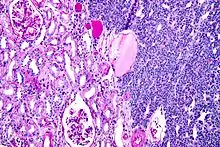

| Micrograph of a metanephric adenoma with structures reminiscent of those seen in papillary renal cell carcinoma. H&E stain. | |

Metanephric adenoma is diagnosed histologically. The tumours can be located at upper pole, lower pole and mid-hilar region of the kidney; they are well circumscribed but unencapsulated, tan pink, with possible cystic and hemorrhagic foci. They show a uniform architecture of closely packed acinar or tubular structures of mature and bland appearance with scanty interposed stroma.[3][4][5][6][7] Cells are small with dark staining nuclei and inconspicuous nucleoli. Blastema is absent whereas calcospherites may be present. Glomeruloid figures are a striking finding, reminiscent of early fetal metenephric tissue. The lumen of the acini may contain otherwise epithelial infoldings or fibrillary material but it is quite often empty. Mitoses are conspicuously absent.[3][4][5][6][7] In the series reported by Jones et al. tumour cells were reactive for Leu7 in 3 cases of 5, to vimentine in 4 of 6, to cytocheratin in 2 of 6, to epithelial membrane antigen in 1 of 6 cases and muscle specific antigen in 1 of 6.[5] Olgac et al. found that intense and diffuse immunoreactivity for alpha-methylacyl-CoA racemase (AMACR) is useful in differentiating renal cell carcinoma from MA but a panel including AMACR, CK7 and CD57 is better in this differential diagnosis.[8] Differential diagnosis may be quite difficult indeed as exemplified by the three malignancies initially diagnosed as MA that later metastasized, in the report by Pins et al.[9]